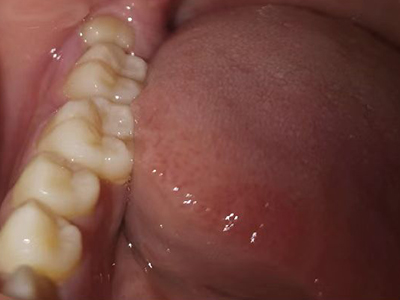

阻生牙是指由于邻牙、骨或软组织的阻碍而只能部分萌出或完全不能萌出,且以后也不能萌出的牙。引起牙阻生的成因,主要是由于颌骨缺乏足够的空间容纳全部恒牙。常见的阻生牙为下颌第三磨牙、上颌第三磨牙及上颌尖牙。

阻生牙可反复引起冠周炎,或引起邻牙牙根吸收和破坏,位置不正,不能完全萌出,好发部位是上、下颌第三磨牙。